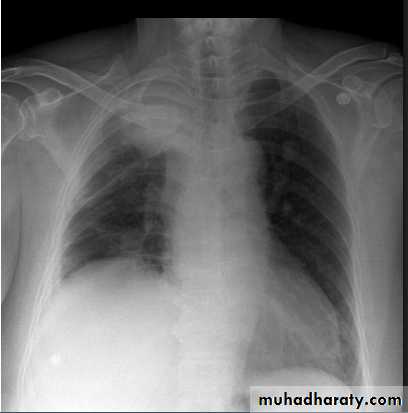

Massive pleural effusion with mediastinal shift to the left.

(A) Chest radiograph(B) CT coronal reconstruction. A massive effusion displaces the mediastinum to the left. CT shows the important pleural effusion together with the enhanced atelectatic left lung.

Note also the depression of the right hemidiaphragm (arrows).